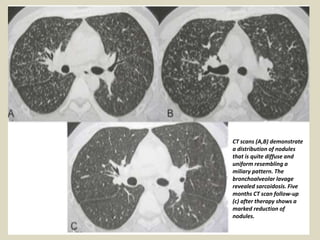

MILIARY PATTERN This pattern is rare in sarcoidosis (< 1% of cases) and its presence

requires a wide differential diagnosis, including entities such as tuberculosis,

pneumoconiosis, metastatic lesions, histoplasmosis and histiocytosis.

ATYPICAL MILIARY OPACITY

CT scans (A,B) demonstrate

a distribution of nodules

that is quite diffuse and

uniform resembling a

miliary pattern. The

bronchoalveolar lavage

revealed sarcoidosis. Five

months CT scan follow-up

(c) after therapy shows a

marked reduction of

nodules.